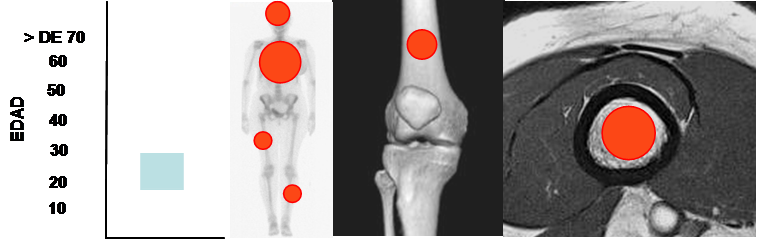

Fig 100. Displasia fibrosa.

Mayor frecuencia entre los 20 y 30 años. Predominio en costillas, cráneo, fémur y tibia.

Lesión diafisiaria, de ubicación central o excéntrica.